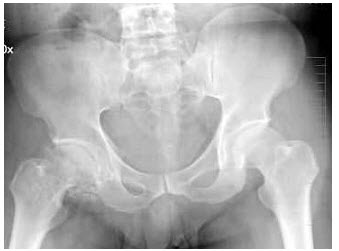

13、单项选择题

男,46岁,双髋部疼痛,实验室检查血钙升高,尿本周蛋白(+),结合图像,最可能的诊断是()

A.骨髓瘤

B.骨质疏松症

C.骨转移瘤

D.骨囊肿

E.动脉瘤样骨囊肿

14、单项选择题 左主支气管与气管中线成多少度角()